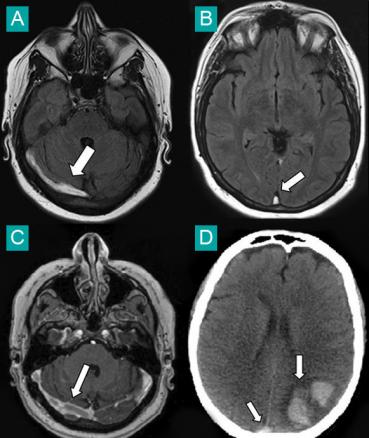

A. Imagerie par résonance magnétique (IRM) en séquence FLAIR : thrombose du sinus latéral droit (flèche).B. IRM en séquence FLAIR : thrombose du sinus longitudinal supérieur (flèche).C. IRM en séquence veineuse injectée : absence d'opacification du sinus latéral droit (flèche).D. Tomodensitométrie non injectée : thrombose du sinus longitudinal supérieur (flèche) et hémorragie parenchymateuse (flèche).